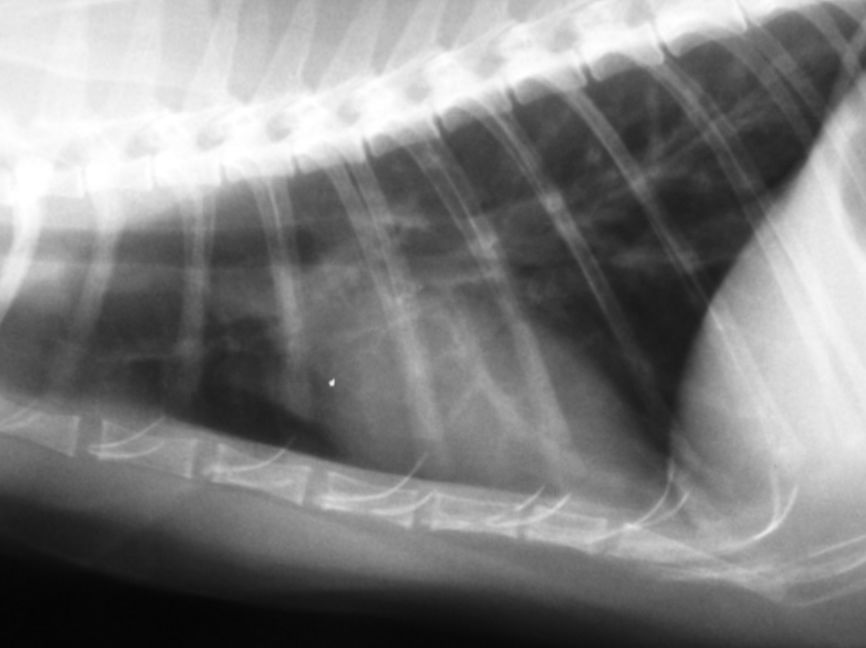

鉴别诊断的方法主要是通过胸部X光,这是检测哮喘、胸腔积液(包括乳糜胸)、肺脏实质、肺丝虫及气管疾病首选的方法。另外,可以通过便便检查猫咪体内是否存在寄生虫。也可能需要使用支气管镜检查猫的呼吸道,或者用经气管冲洗法从猫的喉咙内提取细胞样本。

支气管壁增厚图片来自《Small Animal Emergency and Clinical